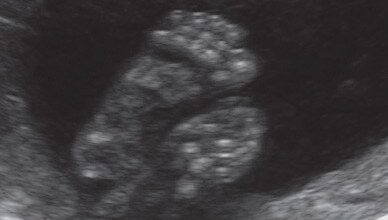

12/25

La evolución del feto a través de ecografías

Ecografía de 3 meses: en la primera ecografía de un embarazo gemelar se puede precisar si existen una o dos placentas. En esta imagen, la presencia de la placenta en la barrera muestra un embarazo bicorial biamniótico, es decir, con dos placentas y dos sacos independientes.